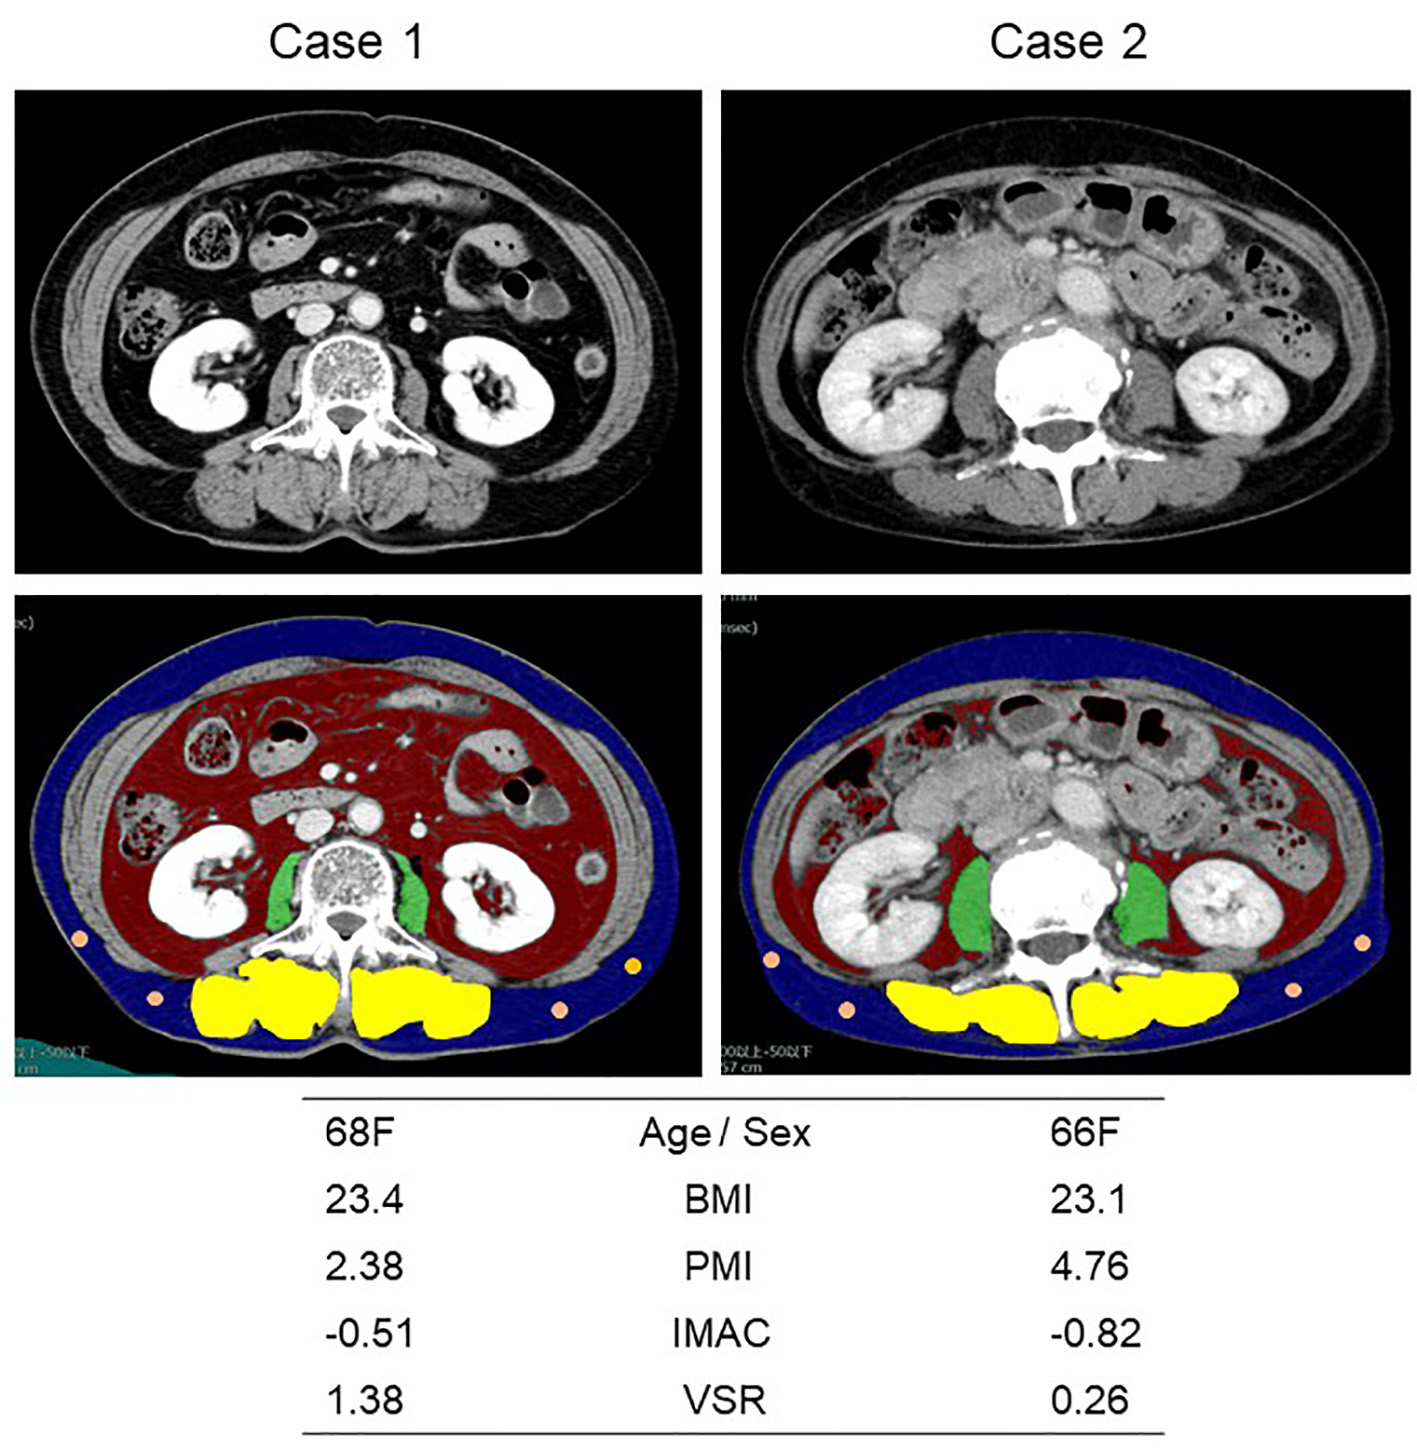

We used SYNAPSE VINCENT software (Fujifilm Medical, Tokyo, Japan), enhanced or plain cross-sectional CT images taken for the practical purpose of diagnosing, staging or follow-up assessment, and CT attenuation values at the level of transverse process of lumbar vertebra L3. The bilateral psoas muscle area, VFA and SFA were automatically identified and then manually corrected. The multifidus muscles area was manually traced. PMI (cm2/m2), IMAC and VSR were calculated by dividing psoas muscle area (cm2) by the square of the patient’s height (m2) [15], the CT attenuation value (Hounsfield Unit, HU) of the bilateral multifidus muscles by that (HU) of four circles with the diameter of 6 mm on subcutaneous fat away from major vessels [16], and VFA by SFA, respectively. Representative CT images are shown in Figure 1. Reviewing the previous Japanese studies, as the sex-specific cut-off points for PMI, IMAC and VSR, we pre-defined 6.36 cm2/m2 for men and 3.92 cm2/m2 for women [15], and -0.358 for men and -0.229 for women [17], and 1.33 for men and 0.93 for women [18], respectively.

![]() Click for large image | Figure 1. Representative cross-sectional CT images obtained at the third lumber vertebra. Two female patients had similar BMI and age, but different PMI, IMAC and VSR. The areas of bilateral psoas muscles, visceral fat, subcutaneous fat, multifidus muscle and subcutaneous four small circles were identified by green, red, blue, yellow and orange. CT: computed tomography; BMI: body mass index; PMI: psoas muscle index; IMAC: intramuscular adipose tissue content; VSR: visceral-to-subcutaneous adipose tissue area ratio. |